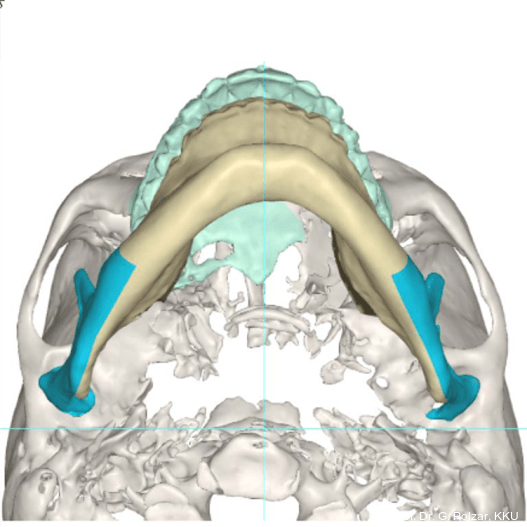

KG-Position: Die 3D-Ansicht im DVT zeigt eine vorverlagerte UK-Position bei neutraler Okklusion (Abb. 4a+b).

Im Sagittalschnitt zeigen beide Kiefergelenke eine deutlich anteriore Position. Der dorsokraniale Abstand betrug rechts 7,0 mm und links 5,8 mm. In der PEP waren sie im lateralen Bereich ca. 1 mm kleiner als in der Mitte der Sagittalprojektion (Abb. 6a–d).

Diese deutlich anteriore Gelenkposition im Neutralbiss ließ den Verdacht auf einen Sunday Bite zu. Das heißt, die Patientin schob den Unterkiefer aktiv nach vorne, um damit schönere Schneidezahnkontakte bzw. eine vermeintlich neutrale Okklusion zu erreichen. Nach mühsamen Lockerungsübungen gelang es der Patientin, auch in die zen­trale Kiefergelenkposition zu wechseln. So zeigte sich das ganze Ausmaß der Malokklusion. In neutraler KG-Position hatte die Patientin eine sagittale Frontzahnstufe von ca. 7 mm mit 1 PB Klasse II-Okklusion im Seitenzahn­bereich (Abb.5a+b, 7a–c).